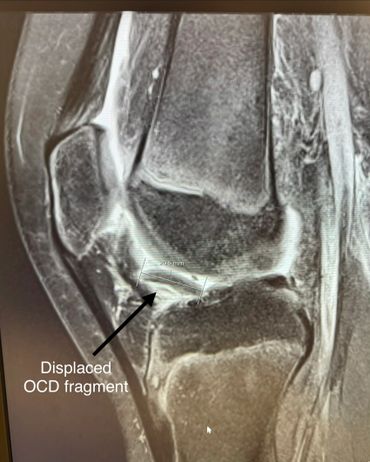

- Osteochondral OCD repair